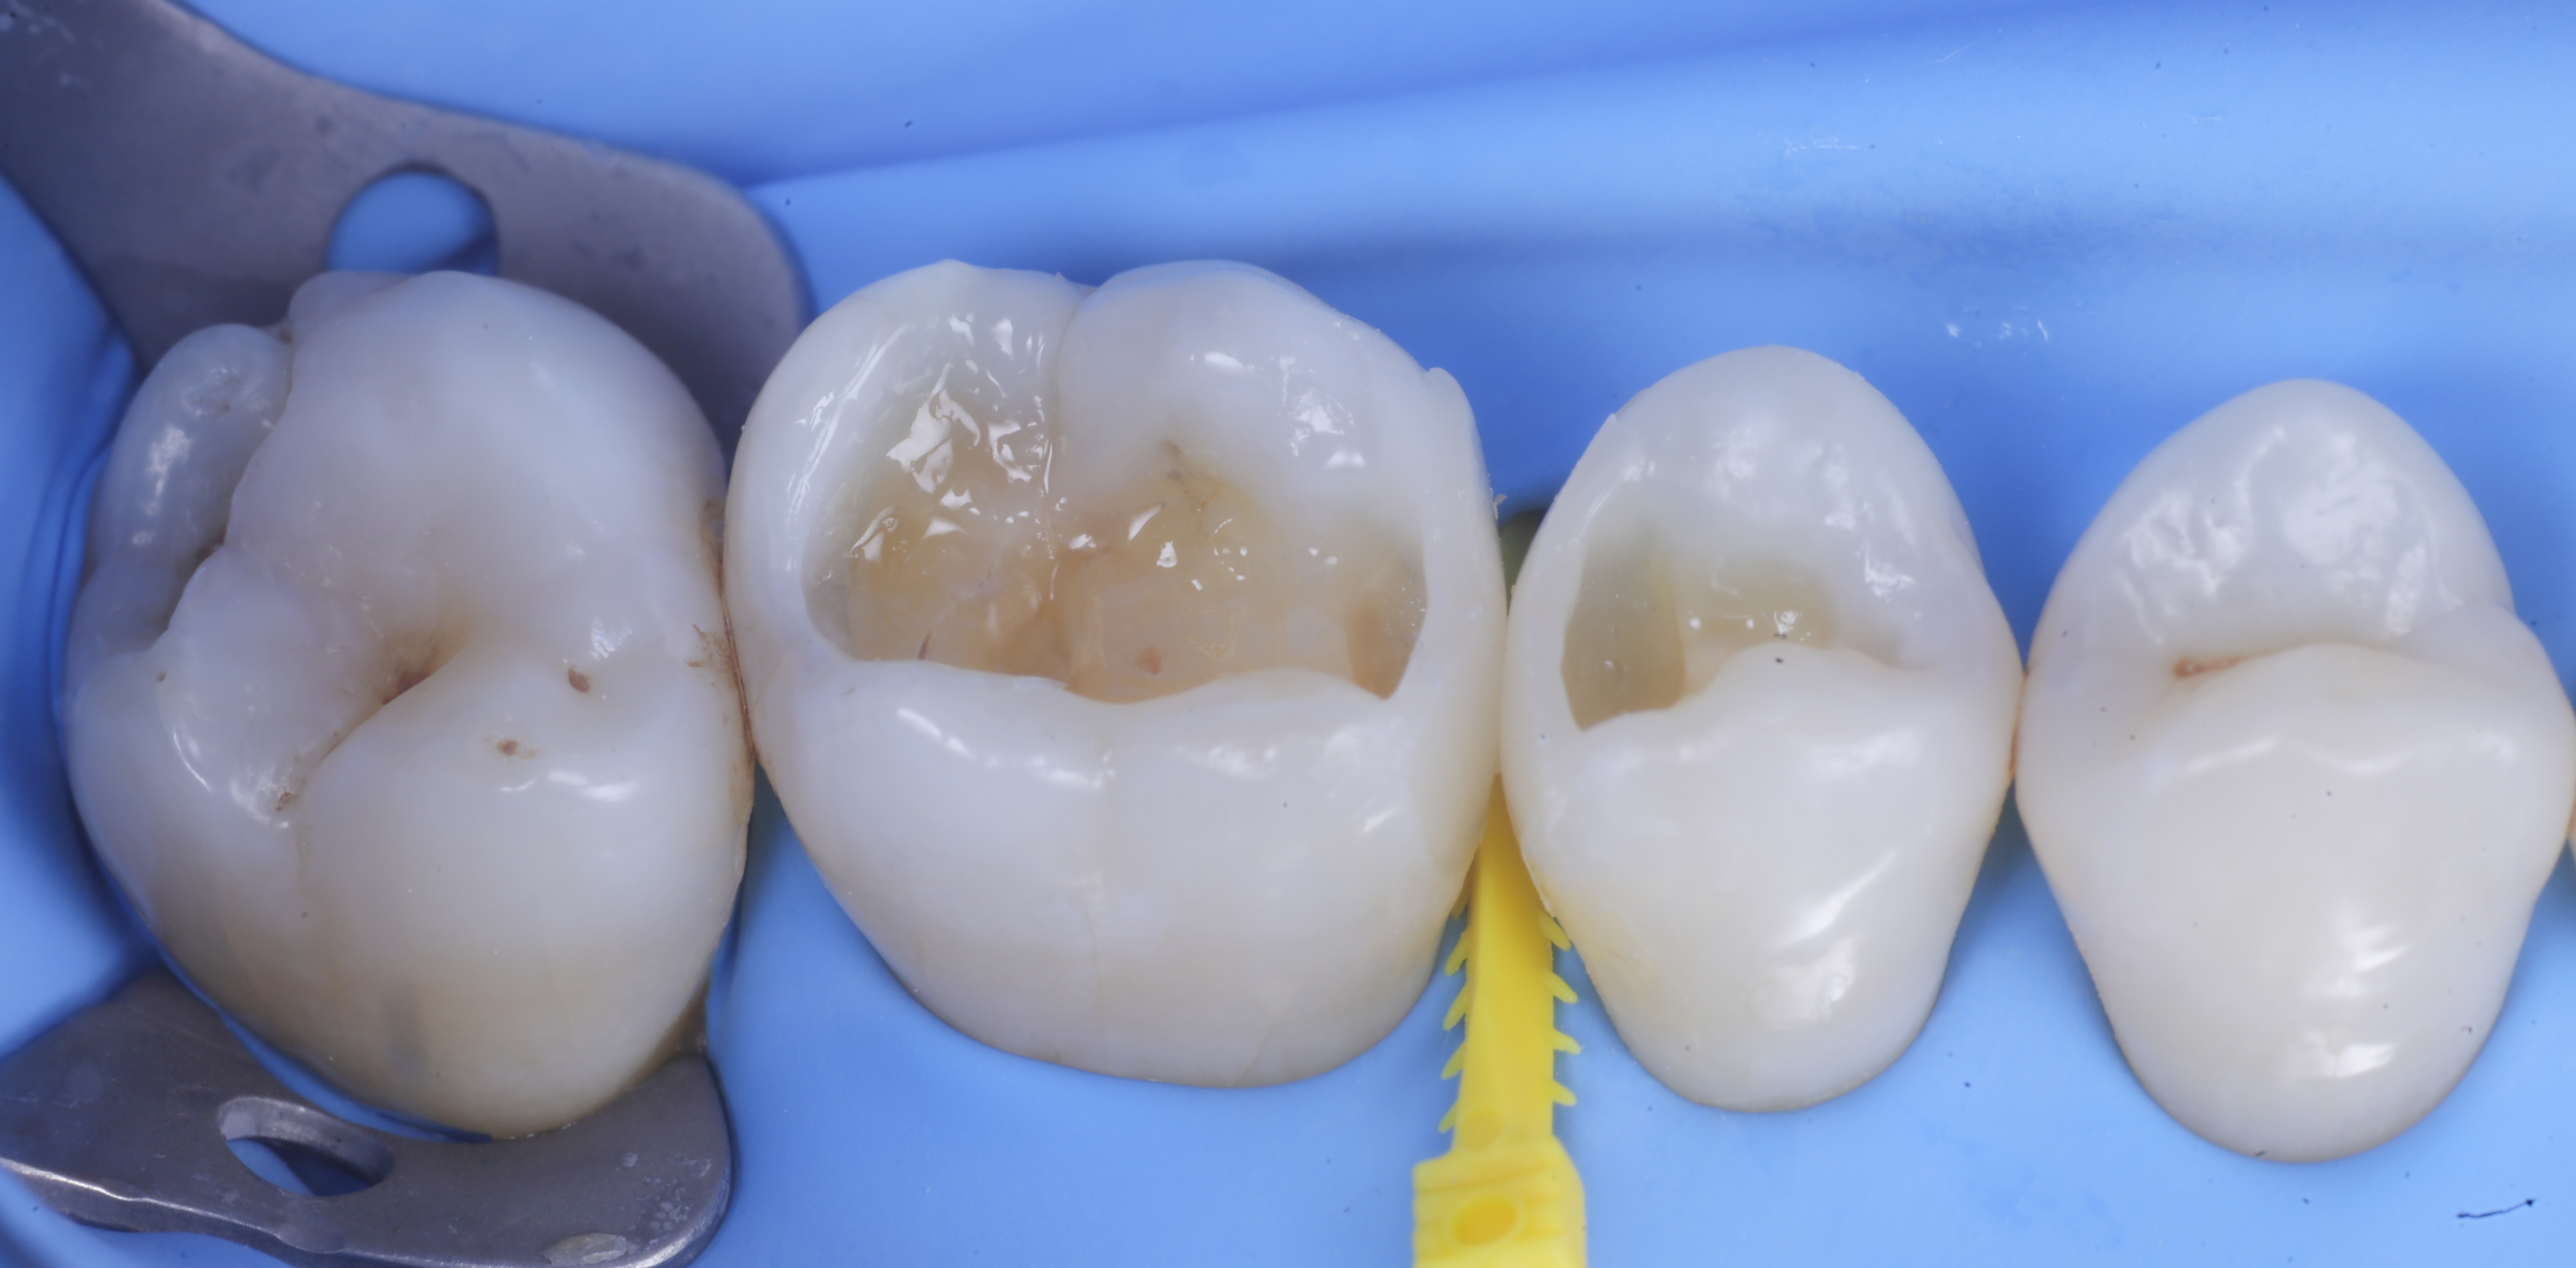

foto 2 Isolamento e aspetto delle cavità ultimate

foto 3 Aspetto vestibolare della cavità ultimate

foto 4 Aspetto della chiusura cervicale e sulle pareti assiali dato dalla prima matrice

foto 5 Aspetto della chiusura cervicale e sulle pareti assiali della seconda matrice